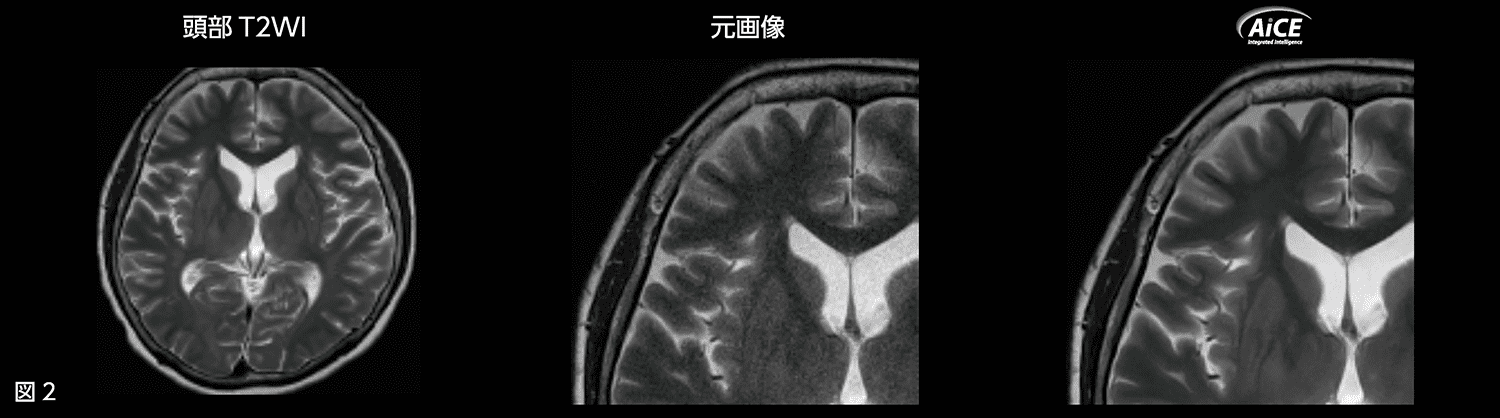

またT2WIにおいては、圧縮センシング(Compressed SPEEDER:以下、CS)とAiCEを併用し、Matrix 512×512(Reso.0.45×0.45mm) の画像を1分半程度で撮像しています(図2)。